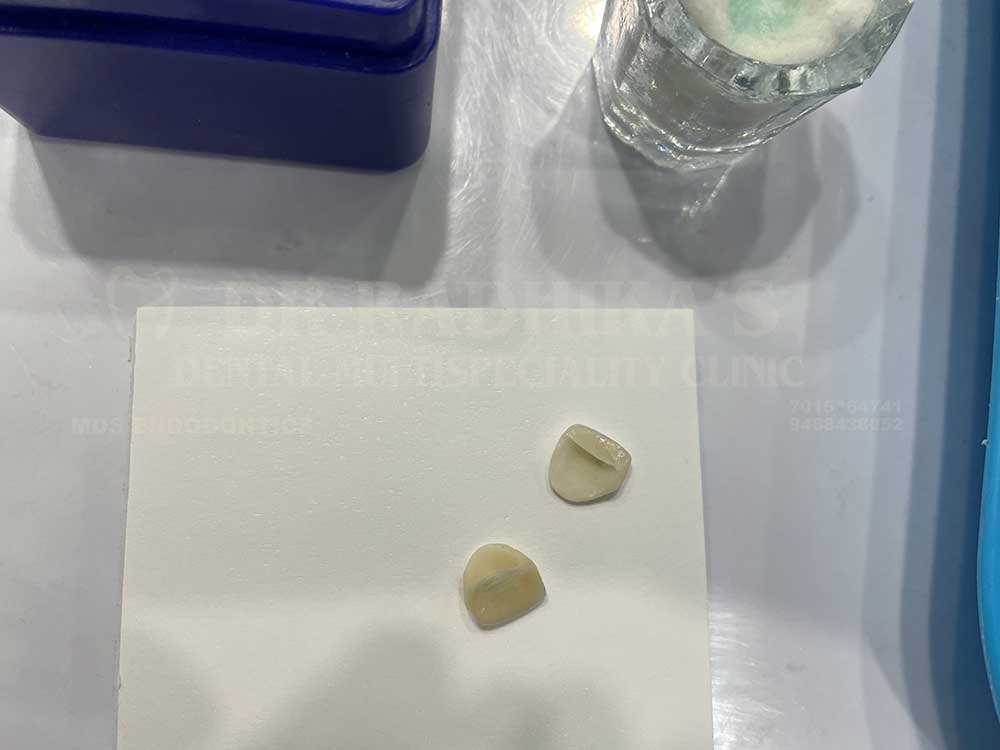

Veneers or laminates

Dental veneers are ultra-thin shells made from porcelain or composite resin that are bonded to the front surface of your teeth. They are an excellent solution for correcting imperfections such as:

Porcelain veneers are highly durable and stain-resistant, making them a long-lasting solution for a radiant smile. Composite veneers, on the other hand, are more cost-effective and require minimal tooth preparation, making them ideal for quick aesthetic fixes.